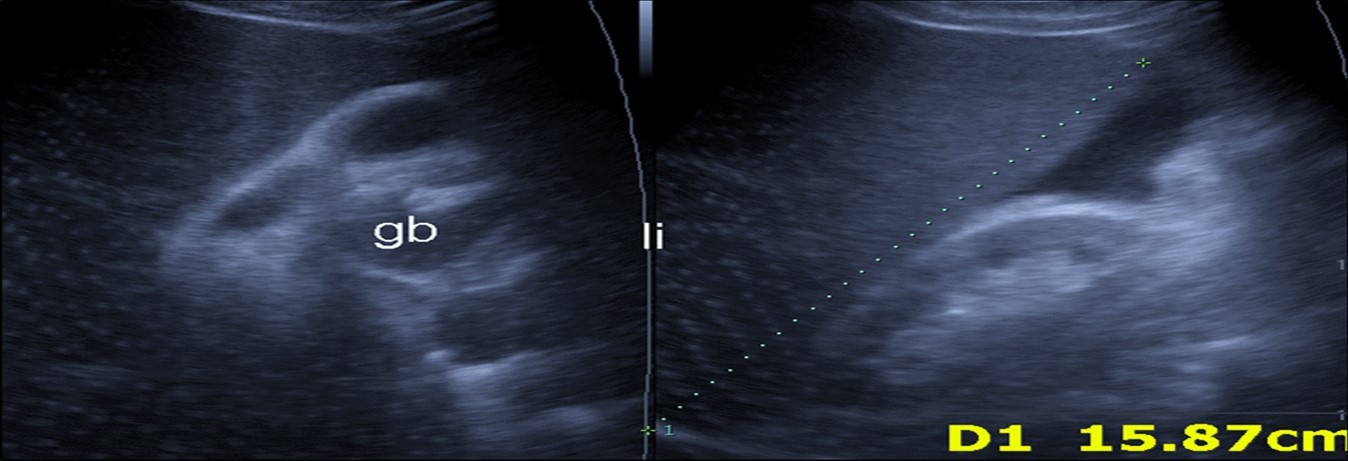

Abdominal ultrasound may revealed any of the followings:-Mild hepatomegaly with echogenic parenchyma and ascites in cases with hepatic impairment (Figure 4, Figure 5) ,thick walls of gall bladder with mildly dilated Common bile duct suggesting of biliary stasis and cholecystitis (Figure 6) .Abnormal renal echogenicity (Figure 7), suprarenal gland enlargements with heterogeneous texture ,splenic wedge shape area of hypoechogenicity ,thickened walls of bowel mainly the rectosigmoid region ,dilated bowel loops with free peritoneal fluid, and gases in the bowel wall with mesenteric and portal vein gases suggesting of bowel wall infarction13.

Figure 5.Real time ultrasound showing mild hepatomegaly (li), ascites and thickened gall bladder wall(gb).